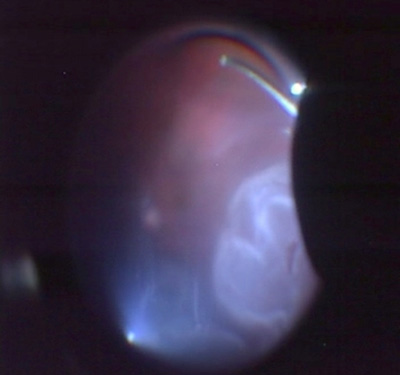

上左図 増殖性糖尿病網膜症で網膜に牽引がある状態

上右図 術後 牽引がとれて視力も回復した

上左図 糖尿病黄斑症の術前RV=(0.3)

上右図術後1RV=(0.9)視力回復し、歪みがましになった